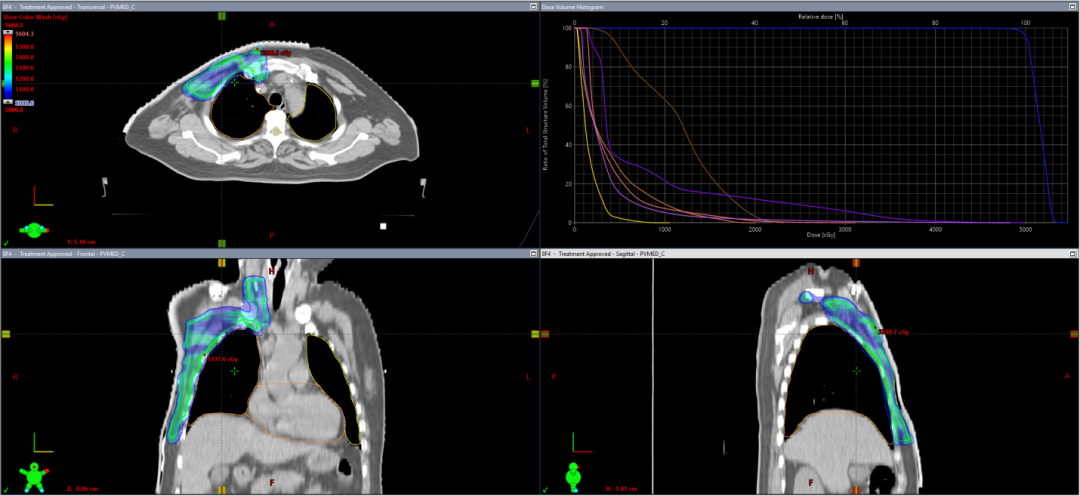

近日,中山大学附属第三医院放疗科收治一例特殊乳腺癌病例。该患者于乳腺癌根治术后五年即出现局部复发,不仅需承受二次手术带来的身心创伤及经济负担,更面临肿瘤侵袭性增强导致的远处转移风险显著升高。经深入追溯治疗史发现,该患者术后未遵医嘱严格执行术后辅助放射治疗,这一关键治疗环节的缺失与本次肿瘤复发存在明确相关性。放疗作为乳腺癌治疗的核心手段之一,通过高能射线精准杀灭残留癌细胞,降低复发风险。尤其对于保乳术后患者,放疗是必做的一个环节,能将局部复发率从30%降低至5%以下。 哪些乳腺癌患者需要放疗? 放疗适应证需结合病情精准判断,主要包含以下情况: 1、保乳术后患者:原则上均需全乳放疗,但70岁以上、肿瘤≤2cm且激素受体阳性的低危患者可豁免放疗。 2、乳房全切术后高危患者: 1)肿瘤≥5cm或侵犯胸壁/皮肤; 2)腋窝淋巴结转移阳性。 3、复发或转移患者:骨转移及脑转移、全身远处转移等均可姑息性放疗甚至根治性放疗,显著提升生存质量,延长生命。 技术革新:从精准放疗到器官保护 在徐向英主任严格要求及乳腺癌诊疗指引下,中山三院肿瘤放疗科从放疗体位固定、CT模拟定位开始,到靶区勾画、放疗计划设计及验证,再到放疗实施上,每一步都坚守“团结协作、规范创新”的学科理念。 1、体位固定阶段:采用发泡胶、真空垫、体膜等标准的固定装置,实现放疗期间体位保持高一致性。 2、放疗计划阶段:采用调强适形放疗(IMRT),通过精准勾画靶区、设计放疗计划,实现精准放疗,同时通过严格限制重要危及器官的靶区受量,着重保护患者的心脏、肺等重要器官。 3、放疗实施阶段:每次放疗前都通过CBCT技术,监控靶区、器官位置并精准匹配照射区域;目前已推进光学体表监测技术的引入,通过实时追踪呼吸运动,进一步将放疗体位误差控制在毫米级。 图1放疗体位固定装置 图2 放疗实施过程 图3 假体/扩张器植入术后放疗TPS图 图4 保乳术后放疗TPS图 图5 改良根治术后放疗TPS图 图6 CBCT技术精准匹配 乳腺癌放疗全流程中的人文关怀 1、隐私与操作规范:增加女性技师操作,严格“一出一入”制度,确保隐私保护。 2、皮肤护理要点: 1)照射区皮肤避免摩擦(禁胶布、抓挠),可涂医生推荐保护剂(如三乙醇胺乳膏)。 2)穿宽松V领棉质衣物,避免胸罩/饰品;清洁用温水,禁用香皂/化妆品。 3)防晒、防冷热刺激,禁止泡澡/游泳。 3、健康管理建议: 1)每日患侧手臂功能训练(爬墙、外展等),避免负重或下垂,多叉腰保持腋窝干燥。 2)加强营养,适度运动,规律作息。 乳腺癌放疗中常见副作用及应对措施 1、皮肤反应:分级管理,从轻度发红到破溃渗液,需按医嘱使用药物或敷料。注意:放疗结束后2-3周仍需持续护理,直至皮肤愈合。 2、黏膜损伤:口腔黏膜保护:加强漱口,避免过热或坚硬食物;咽痛时可药物治疗。 3、疲劳与血象监测:尤其是同步使用其他抗肿瘤药物(靶向药、内分泌药等)的患者,建议每周复查血常规,及时处理白细胞降低等问题。 突破认知误区:这些传言不可信! 1、“放疗会传染”:外照射治疗后体内无放射性残留,可安全接触家人。 2、“心脏受损不可避免”:精准放疗及器官保护等先进技术的支持下,患者可长期生存,心脏毒性可防可控。 3、“必须剃光腋毛”:仅需清洁皮肤,除非毛发影响定位标记。 中山三院放疗科在国内著名放疗专家徐向英主任的带领下,团队始终秉持“团结协作、规范创新”的理念,以"精准放疗"为核心,融合先进技术与严格质控,实现乳腺癌放疗"高能低毒";同时创新人文关怀模式,通过隐私保护、心理支持等举措,让患者在规范治疗中保有尊严与生活质量,真正践行"疗效与温情并重"的医疗理念。 科室简介 学科理念: “团结协作 规范创新” 中山三院肿瘤放射治疗科公众号 学科特色 科室创建于2018年3月,由中山大学引进的国内知名放射肿瘤学专家徐向英教授担任学科创始人及首任科主任。科室由肿瘤放疗病区、肿瘤放疗中心两大部门组成,目前病区拥有床位36张。 专科特色为肺部小结节及早期肺癌影像学诊断、脑胶质瘤、鼻咽癌及头颈部肿瘤、肺癌、乳腺癌、食管癌、肝癌、妇科肿瘤、前列腺癌、直肠癌等的精准放射治疗、放化疗及免疫综合治疗。 岗位结构多样,主要由医师、护师、物理师、技师等岗位组成。 人才队伍 目前学科工作人员共36人,医师9人(教授1人,主任医师1人、副主任医师2人、主治医师1人及住院医师5人);护士12人(主管护师3人);物理师4 人(中级职称2人);技师9人;文员1人;辅助人员1人;团队中博士6人,硕士6人,博士后导师1人。 放疗设备 实现技术 可完成立体定向放疗(SBRT)或体部立体消融放疗(SABR)、容积调强放疗(VMAT)、图像引导放疗(IGRT)、调强放疗(IMRT) 及三维适形放疗(3DCRT)等多种精准放疗技术,能够做到高精度、高剂量、高疗效和低损伤。目前,大部分患者放射治疗误差范围可控制在1mm以内,另外中山三院肿瘤放射治疗科所有盆腔患者(宫颈癌、子宫内膜癌、前列腺癌及直肠癌等)治疗全程进行膀胱超声尿量控制,确保患者治疗位置的精准性及重复性,为癌症患者提供强大的精准放射治疗设备支撑和技术保障。